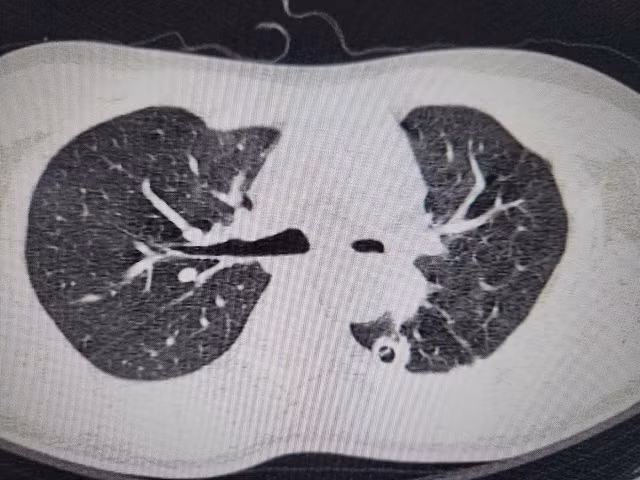

Sau 10 tháng vật lộn với di chứng lao phổi, bệnh nhân được chuyển đến khoa Phẫu thuật Lồng ngực, Bệnh viện Bạch Mai. Qua các thăm khám lâm sàng và chụp chiếu, kết quả quả cho thấy, anh B. đối diện với nguy cơ mất phổi vĩnh viễn. Kết quả chụp CT 3D phổi cho thấy phế quản gốc trái chỉ còn khe hẹp 2mm, phổi xẹp đặc như tấm bìa cứng. Nếu không phẫu thuật trong 2 tuần, phổi sẽ hoại tử.

| Hình ảnh phim chụp hẹp phế quản gốc trái, xẹp hoàn toàn phổi trái do di chứng của lao phổi. |